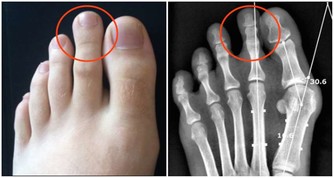

腳溝炎,是指腳指甲在受到外界的擦傷、刺傷、割傷後。因為沒有得到及時的處理,而受到局部的感染,細菌堆積,導致甲下發生膿腫,這是腳溝炎最主要的病因。此外,趾甲剪得太短或長期不剪趾甲、長期穿不合適的鞋子也會造成腳溝炎的發生。

(3)如果已經出現甲下化膿,應當到醫院去及時切開或將趾甲拔去,擠出膿液。

(1)注意保護趾甲周圍的皮膚,趾甲不益留太長或剪太短。